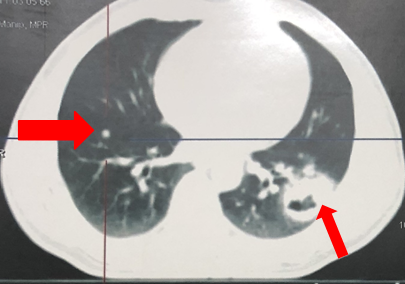

- Hình ảnh chụp cắt lớp vi tính lồng ngực sau điều trị 2 tháng (hình 2a, 2b):

Khối u thùy dưới phổi trái với kích thước 3,0x2,9cm.

Hạch trung thất trái 2,5cm, không thấy hạch rốn phổi.

Không thấy nốt tổn thưởng di căn ở phổi phải.

Hình 2a: Hình ảnh chụp cắt lớp vi tính lồng ngực khối u thùy dưới phổi trái với kích thước 3,0x2,9cm (mũi tên vàng), Không rõ nốt tổn thưởng di căn ở hai phổi.

Hình 2b: Hình ảnh chụp cắt lớp vi tính lồng ngực cho thấy hạch trung thất trái 2,5cm (mũi tên đỏ), không rõ hạch rốn phổi.